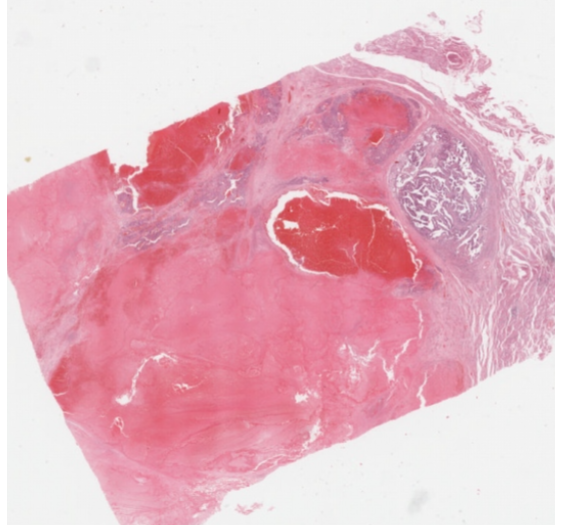

2、数字资源:划分有专门的数字资源模块,包含400多个精细的3D病理虚拟模型、700多个3D病理大体标本、50个手术入路解剖3D模型、400多张病理学数字切片、200多部临床 手术3D动画、30部病理学3D动画、100多部病理学数字切片微视频等资源,以震撼的视觉吸引力、丰富易读的知识点精彩呈现。